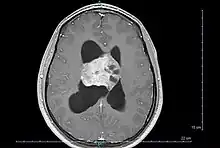

| Axial T1-weighted gadolinium-enhanced MRI image showing an enhancing mass with cystic changes consistent with central neurocytoma in the right lateral ventricle. | |